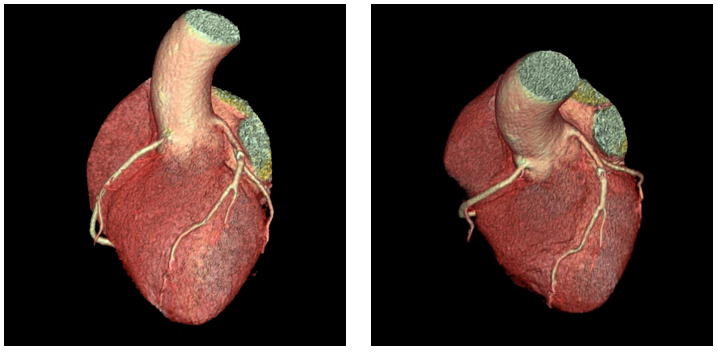

病例一:冠状动脉检查

赵主任谈到,Revolution CT自2017年1月中旬装机,临床应用培训后投入使用,近4个月来,日均30-40例患者,由于是初期使用加之病房楼搬迁等情况,设备运行未达满负荷,即使是这样,Revolution CT也另我们耳目一新,因为在此设备上进行的冠脉扫描没有失败的,不需要前期准备心率,极大的改善了冠脉扫描的流程,冠脉患者“无需预约等待,来了就能做”,赵主任自信的告诉我们,“由于院内设施建设,一般安排患者都就近检查,临近病区的冠脉检查都在此设备上做,不做心率筛选。根据不同疾患的临床需求和BMI值,我们设置不同的扫描方案,实现了精准医疗环境下真正的个性化扫描”,冠脉CT成像的挑战在于高心率和心律不齐,“这在过去我们感觉有难度的扫描,如今都可以在单心跳下轻松完成扫描,成功率100%,无挑战”。